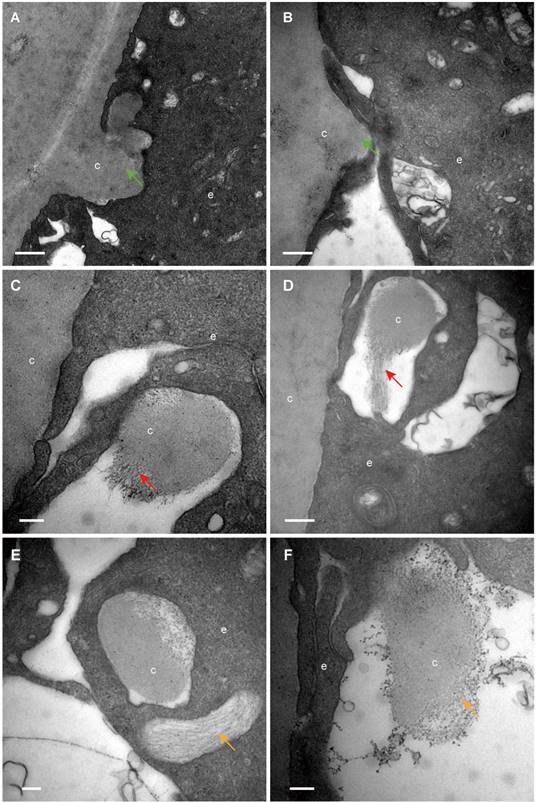

Numerous extracellular vesicles were observed in the space between HLECs and between HLECs and the capsule

By TEM, different sizes and shapes of extracellular vesicles (EVs) were observed in the extracellular space of the HLECs in all donor samples (Table 1). Four different morphologies of the EVs were observed in the current study, which are summarised in Figure 4: An extracellular membrane-bound vesicular structure was observed at the basal side of the HLECs, the membrane of which appeared to be continuous with the plasma membrane of the HLECs. The majority of these membrane structures were oval shaped, with diameters of 2-3 μm, containing numerous smaller vesicles (Figure 4A); isolated membrane-bound vesicles in the extracellular space with intact membrane (Figure 4B); isolated membrane-bound vesicles in the extracellular space with a discontinuous membrane (Figure 4C); numerous smaller vesicles distributed in the extracellular space, some of which were closely attached to the HLECs (Figure 4D). Similarly, EVs were found in the space between HLECs and the capsule, some of which analysed 328 smaller EVs from 10 TEM images, and their diameters were between 26.8 and 307.3 nm. Interestingly, 83.8% (275/328) of them ranged from 30 to150 nm (Figure 4J). Immunofluorescence results illustrated that exosome markers (CD63 and CD81) were expressed in the HLECs on the lens capsule flat-mount (Figure 4K、L). In addition, these results were further studied in the aLCs in different types of cataract patients after routine cataract surgery, including age-related, complicated and congenital cataracts. Different EV sizes and shapes were also observed in the extracellular space at the basal side of the HLECs. However, EVs in the cataract samples appeared to be more irregular and disorganised, and the four typical morphologies as described above were rarely observed. Representative TEM images are shown in Figure 4L-P.

Extracellular vesicles (EVs) in the human lens. Extracellular vesicles complex with the membrane continuing to the plasma membrane of the HLECs (A, E). Isolated membrane-bound vesicles with intact membrane (B, F). Isolated membrane-bound vesicles with discontinuous membrane (C, G) (black arrow). Smaller vesicles in the extracellular space, some of which are closely attached to the HLECs (D) and capsule (H) (red arrow). Of the EVs, 83.8% were 30-150 nm in diameter (I). Representative images of immunofluorescent staining of the exosome markers CD81and CD63 (green) in flat-mounted HLECs (J, K). Typical EVs (green arrow) in the aLCs of age-related cataract (M, L), primary acute angle-closure glaucoma complicated cataract (N), uveitis complicated cataract (O) and congenital cataract (P). Scale bars: A, E = 2 µm, B = 1 µm, C, D, F, G, M = 0.2 µm, H, L, N-P = 0.5 µm, J, K = 20 µm.

The current study provided clear evidence that numerous EVs appear between adjacent epithelial cells and between the capsule and epithelium in the human lens, and demonstrated their morphological features by TEM. EVs are being identified in an increasing number of cell types and it was not surprising to find them in the human lens epithelium. Although EVs have been previously isolated from the aqueous humour of cataract patients and HLEC cell lines [24-26], to our knowledge, such an extensive presence of small EVs has not previously been reported for the human lens epithelium. EVs play an important role in the communication between cells in both, physiological and pathological processes [27-29]. EVs are generally considered to contain various molecules, including messenger molecules, enzymes, RNAs, and DNA fragments [30]. The morphology of EVs observed in this study appeared to be diversity, which consists of four types of the EVs: (1) outward budding: small separate EVs were generated in the cytoplasm and secreted into the outward budded plasma membrane, forming the EV complex (Figure 4A, E); (2) shedding: the EV complex was shed from the epithelial cells (Figure 4B, F); (3) release: the vesicles were released into the intercellular space (Figure 4C, G); (4) contact: released EVs became bound to the target epithelial cell or capsule (Figure 4D, H). Due to the limitation of 2D images in this study, however, we could not exclude a possibility that these types of EVs might be from different views of the same type of cluster. This question could be revealed by three-dimensional EM work in the future. In addition, EVs in the cataract samples appeared to be more irregular and disorganised, and the four typical morphologies as mentioned above were rarely observed. Further study is needed to evaluate the significance of these findings.

The diameter of EVs found in our study ranged from 26.8 to 307.3 nm, and the majority (approximately 83.8%) were 30-150 nm, indicating that these EVs might have been exosomes. Furthermore, the immunofluorescence results showed that two exosome biomarkers (CD63 and CD81) were expressed in the HLECs on the lens capsule flat-mount. Taken together, we suggest that there might be exosomes in the extracellular space of the HLECs. However, further evidence, TEM on isolated tissue and immunogold TEM with specific markers for exosomes, is needed.